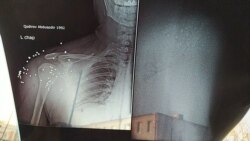

Рентгеновский снимок, сделанный Шохаббосу Джаббарову.

– Я два дня находилась в больнице. Врачи не оказали парням никакой помощи, не извлекли пули из их тел. Когда я спросила врачей, почему они не оказывают им никакой помощи, они заявили нам, что им поступил такой приказ «сверху». В больницу приехал судмедэксперт, он пощупал живот моему внуку и уехал. Мы сделали рентген. Выяснилось, что в теле моего внука имеется 37 пуль. Пули лежали в области плеча и живота, еще семь пуль остались в области селезенки. Врачи не извлекли из его тела ни одной пули. Я была в шоке, когда врач заявил, что пули сами выйдут из тела. Мой внук температурил, когда его увозили милиционеры. Но, несмотря на это, конвой посадил его в машину и увез в изолятор. Разве можно раненного человека помещать в следственный изолятор, тем более, если он является потерпевшим?, – возмущается в разговоре с нашим журналистом бабушка одного из пострадавших.